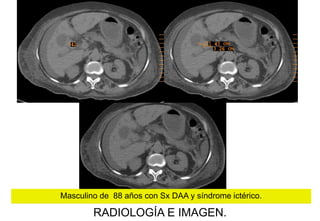

Masculino de 88 años con Sx DAA y síndrome ictérico.